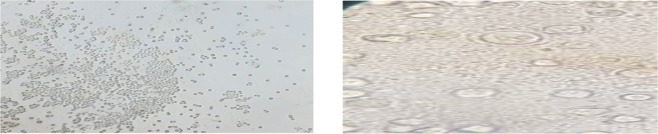

Methods: Totally, 70 samples of vegetables samples including watercress (22), leeks (12), parsley (10), basil (13) and mint (13) were collected from municipal markets of Tehran, the capital of Iran during June to October 2021. After washing vegetables, samples were cultivated onto 2% non-nutrient agar (NNA) medium. After morphological confirmations, DNA was extracted and identical fragments of the FLA were amplified and sequenced.

Results: Out of 70 cultured samples, 11 samples (15.71 %) were morphologically positive, of which four and seven were V. vermiformis and Vahlkampfiidae isolates, respectively. According to the PCR/sequencing results two, one, one, and one strains belonged to N. australiensis, N. americana, Vahlkampfia sp., V. inornata, and T. aberdonicus, respectively. All Vermamoeba genus were characterized as V. vermiformis.